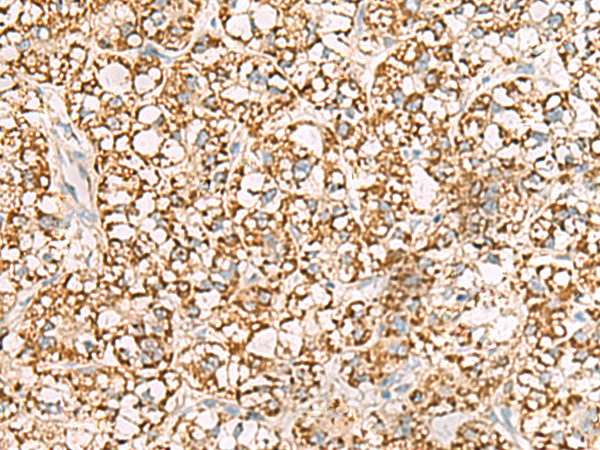

The image is immunohistochemistry of paraffin-embedded Human liver cancer tissue using (ISOC2 Antibody) at dilution 1/95.

The image is immunohistochemistry of paraffin-embedded Human thyroid cancer tissue using (ISOC2 Antibody) at dilution 1/95.